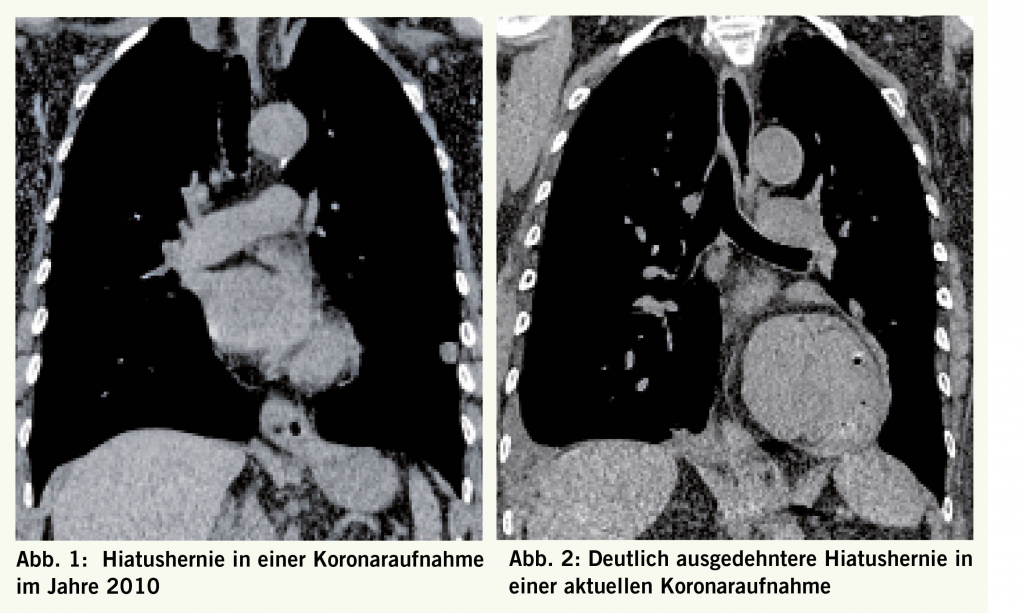

Das erwähnte Asthma der Patientin ist gut kontrolliert und für die Patientin nicht einschränkend. Anamnestisch besteht eine Hiatushernie, welche auch in unserer Einrichtung radiologisch und gastroskopisch bestätigt wurde (Abb. 1). Die Ätiologie, sowie der Entstehungszeitpunkt ebendieser ist nicht bekannt. Eine symptomatische Behandlung erfolgte mit 40mg Esomeprazol morgens und sorgte über längere Zeit für klinische Unauffälligkeit.

Die kurzen Infektintervalle legten den Verdacht auf eine basal ursächliche Pathologie nahe. Die bekannte Hiatushernie wurde als Ursache in Betracht gezogen, jedoch muss hierbei die akut aufgetretene Symptomatik nach jahrelanger klinischer Stummheit begründet werden.

Die Zahl, sowie das kurze Zeitintervall in denen die Infektionen manifest wurden, legt den Verdacht auf eine sekundäre Entstehung nahe. Bei bekannter Hiatushernie muss differenzialdiagnostisch eine aspirationsassoziierte Genese einbezogen werden. Es stellt sich hierbei jedoch die Frage, weshalb sich die besagte Hernie als bisher symptomfrei präsentierte. Daher wurde im Januar 2018 eine Computertomographie angefertigt, welche eine ausgeprägte Progredienz der bekannten Hernie zeigte (Abb. 2). Hiermit konnte die klinische Situation erklärt und die therapeutische Richtung gewiesen werden. Das weitere Vorgehen besteht optimalerweise aus der operativen Sanierung der anatomischen Begebenheiten oder aber der medikamentösen, sowie diätetischen Aspirationsprophylaxe.